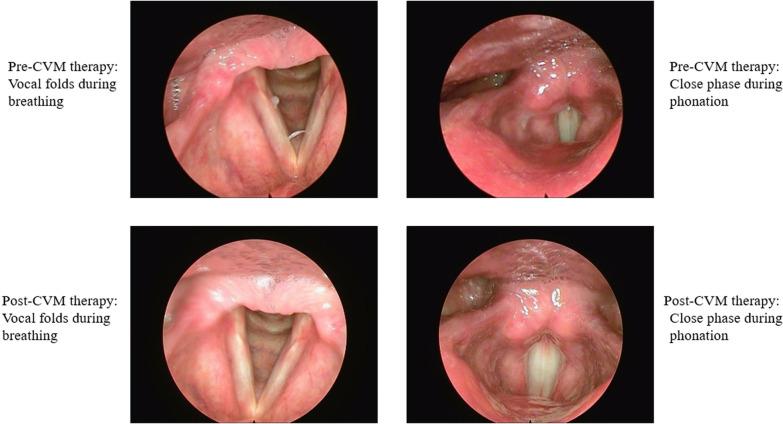

A 55-year-old retired Iranian teacher who was diagnosed with muscle tension dysphonia by an otolaryngologist participated in this study. Fifty days before being referred to an otolaryngologist, he was diagnosed with coronavirus disease 2019 on the basis of the results of a standard laboratory test, namely real-time polymerase chain reaction. Treatment was provided in ten sessions. Pre- and post-treatment audio recordings of sustained vowels, selected sentences, and connected speech samples were submitted for auditory perceptual and acoustic analysis to assess the effects of the treatment program. Also, videolaryngostroboscopy voice quality perceptions by the patient, both before and after therapy, were assessed. The reduction in all features of the Consensus Auditory-Perceptual Evaluation of Voice was observed. The results of acoustic assessment showed that jitter (35.13%) and shimmer (20.48%) decreased; moreover, the harmonics-to-noise ratio (1.17%), cepstral peak prominence smoothed (28.53%) and maximum phonation time (15.5%) increased after treatment sessions. The scores of four parameters of Stroboscopy Examination Rating Form (SERF) form changed after cricothyroid visor maneuver therapy. Also, the visual analog scales score at the pre-treatment assessment was 40, and increased to 90 at the post-treatment assessment.

一名 55 岁的伊朗退休教师,因声带肌紧张性发声障碍被耳鼻喉科医生诊断,参加了这项研究。在被耳鼻喉科医生转介前 50 天,他基于标准实验室检测,即实时聚合酶链反应的结果,被诊断出患有 2019 年冠状病毒病。共进行了 10 次治疗。治疗前后分别提交了持续元音、选定句子和连续言语样本的听觉感知和声学分析的录音,以评估治疗方案的效果。此外,在治疗前后,通过视频喉镜声质量感知评估患者的声质量感知。观察到所有共识听觉感知评估嗓音的特征都得到了降低。声学评估结果显示,抖动(35.13%)和闪烁(20.48%)减少;此外,谐噪比(1.17%)、倒谱峰峰值平滑度(28.53%)和最长发声时间(15.5%)在治疗后增加。声带检查评分表(SERF)的四个参数在环甲膜扇面手法治疗后发生变化。此外,治疗前评估的视觉模拟量表评分为 40,治疗后评估增加到 90。